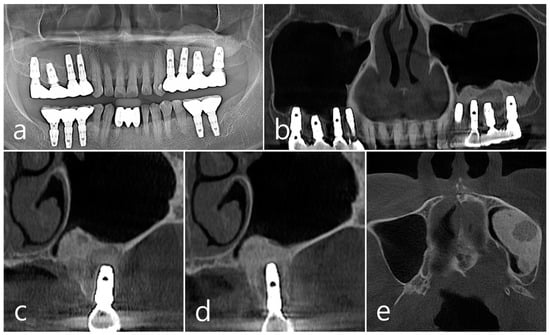

This patient, a 67-year-old female non-smoker, reported no systemic disease that could interfere with the operation. The patient visited the clinic for implant placement for the missing teeth. Panoramic radiography and CBCT were taken. On panoramic radiography, resorption of residual alveolar ridge and pneumatization of the maxillary sinus were observed in the left and right posterior region. Since the amount of residual alveolar bone was 4–6 mm in the maxillary right posterior region, a transcrestal sinus lift was planned (Figure 1a). In the preoperative panoramic, coronal, and axial images of the CBCT scan, abnormal images of the maxillary sinus were not observed, and there was no sinus membrane thickening (Figure 1b–d).

Figure 1. Case 1. (a) In panoramic radiography, resorption of residual alveolar ridge and pneumatization of the maxillary sinus were observed in the left and right maxillary posterior region; (bd) In preoperative CBCT’s panoramic, coronal, and axial images, there were no abnormal findings of the maxillary sinus and no sinus membrane thickening.